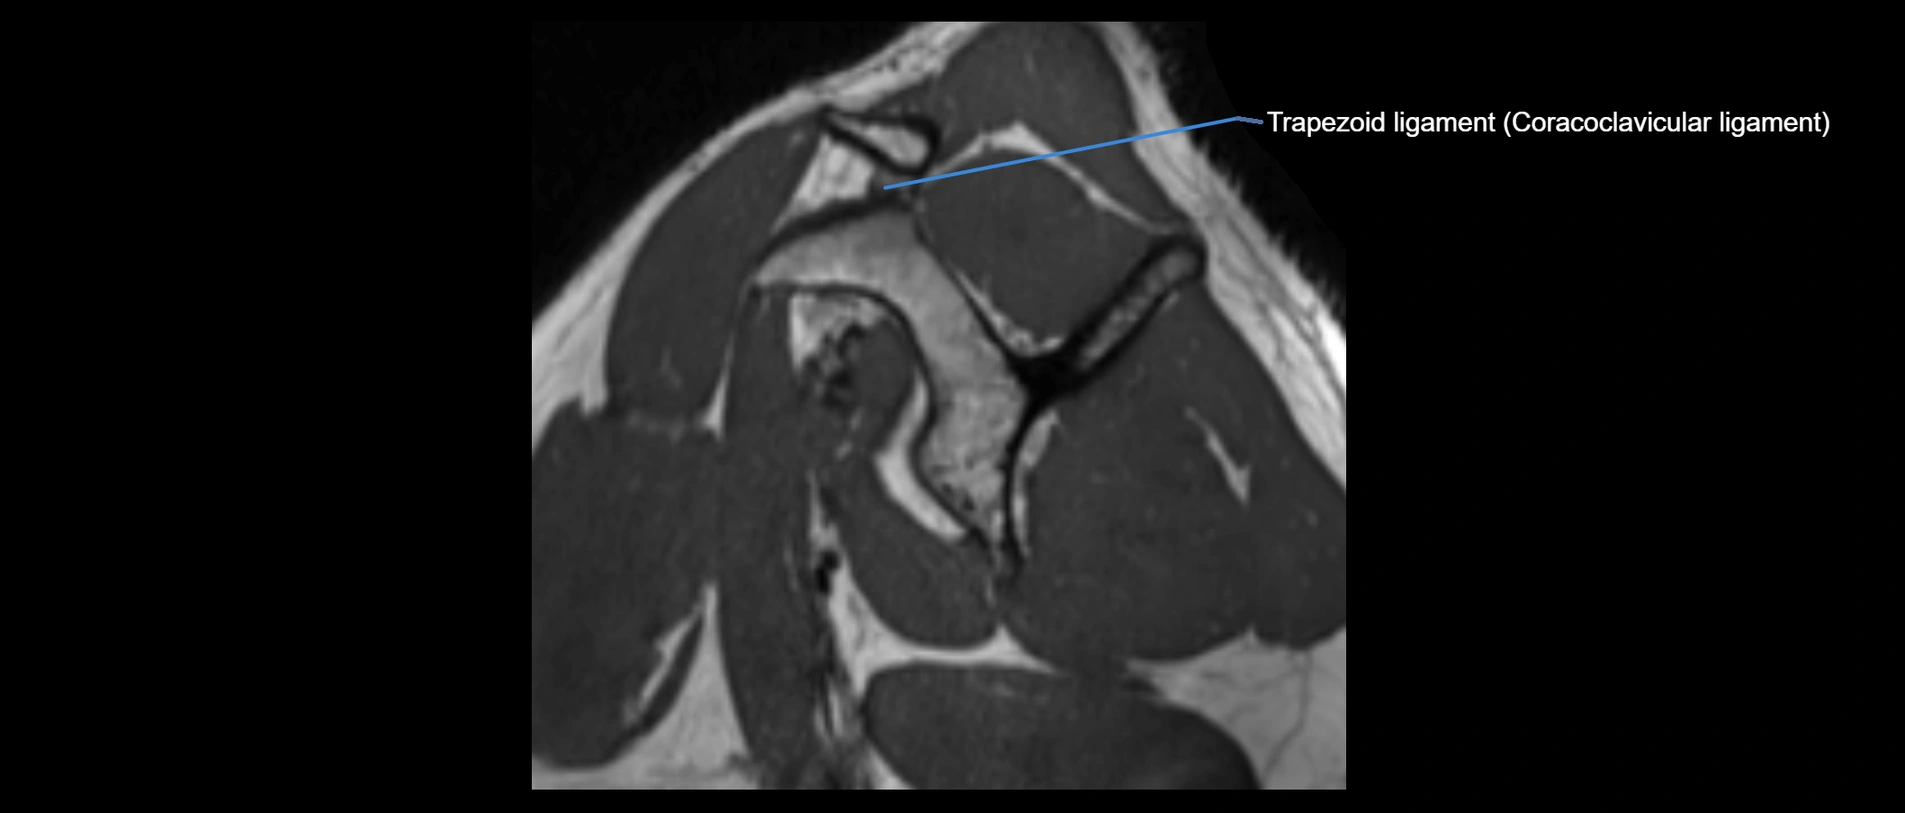

CT image

image